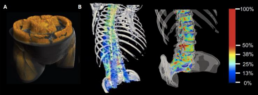

Besides its general impact on bone biomechanics and fracture risk, marrow fat can impact the damping properties of bones, which may contribute to bone remodeling and the development of osteoporosis [1-3]. Developing a detailed computational model based on CT scans could provide valuable insights into how marrow fat affects the mechanical properties of vertebral bone. A central method of our research is the Finite Cell Method (FCM), which is highly suitable for this project due to its ability to simulate microstructured/heterogeneous materials derived from CT scans [4,5]. This method has been effectively employed in CT-based structural analyses of bones, as demonstrated in the work by Schillinger et al. [6], see Figure above. This project aims to investigate the influence of fat in vertebral bone by employing and advancing the Finite Cell Method and Spectral Cell Method to simulate the bone’s elastodynamic behavior, elucidating a potential risk factor for fractures and metabolic bone disease.

Work program and methods

CT scans from vertebral bones will be used as a starting point for a dynamical simulation based on the FCM. Using CT data, a spatial discretization will be derived to form the foundation of the analysis. The study will explore various modeling approaches, each with different levels of complexity, to accurately represent the presence of fat within the bone. Dynamic simulations in the time domain, which include varying volume fractions of fat, will be used to examine and understand the bone’s damping properties. This numerical model will enable us to assess whether bone remodeling can take place in order to maintain optimal damping, which may be compromised by increased fat content. Ultimately, the project will seek to determine whether such remodeling is associated with the development of osteoporosis, resulting from increased marrow fat content.